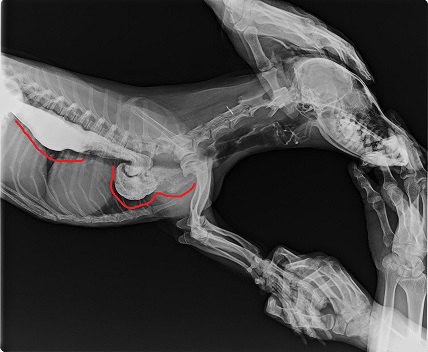

V důsledku toho, že přestane fungovat svalstvo jícnu a u psů není použita gravitace (je uložen vodorovně) dochází k jeho rozšíření a mohou vznikat i hluboké kapsy, kde se jídlo usazuje viz obrázek níže.

Jícen je vodorovná trubice, při Megaesophalu vznikají červeně vyznačené kapsy, kde se hromadí potrava, která se vrací zpět do tlamy. Zdroj: vlastní rentgenový snímek